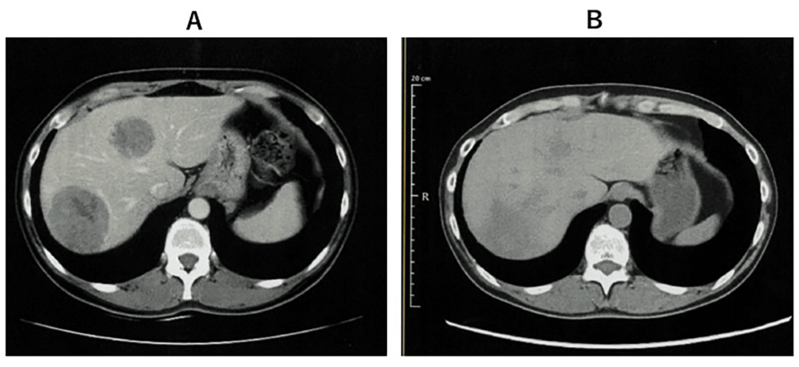

案例2:难治性宫颈癌转移灶消失,免疫功能恢复

小细胞未分化宫颈癌进展快、易耐药,预后极差。《Cureus》报道了一则突破性案例:一位 50 多岁的患者术后出现肝、淋巴结多处转移,化疗失败后,采用 WT1-DC 疫苗联合放疗: 1、第 67 天(注射第 5 剂疫苗后),CT 显示肝转移灶完全消失; 2、免疫指标(中性粒细胞 / 淋巴细胞比值等)恢复正常,原本因化疗受损的免疫功能显著改善。 案例3:胰腺癌患者中位生存期突破3年,7人成功手术 胰腺导管腺癌被称为 “癌王”,对放化疗天然耐药。《癌症免疫治疗杂志》的一项研究带来了新希望:10 例不可切除的胰腺导管腺癌患者(6 例 III 期局部晚期、3 例 IV 期转移性、1 例术后复发)采用 WT1-DC 疫苗联合化疗后: 1、所有患者肿瘤负荷下降,7人达到部分缓解,3人长期稳定; 2、9例患者中位无进展生存期 2.23 年,中位总生存期更是突破 3.52 年,远超传统治疗的预期。 3、 7 例成功接受了转化手术,其中 6 例实现 R0 切除(肿瘤完全切除,无残留),1 例为 R1 切除(镜下有残留)。 案例4:晚期十二指肠癌 4.3 年无进展,恶性腹水消失 十二指肠癌占胃肠道癌症的 0.3%-0.5%,虽发病率低但侵袭性强,易快速扩散,根治性手术是唯一可能治愈的手段,但晚期患者往往失去手术机会,且针对恶性腹水缺乏有效治疗方案。 《Cureus》曾报道一则案例:一位 72 岁的晚期十二指肠癌患者,腹膜播散伴恶性腹水,化疗失败后接受 WT1/MUC1-DC 疫苗联合细胞疗法: 1、第 8 次治疗后,恶性腹水消失,腹胀、水肿等症状消退; 2、原发病灶和转移淋巴结缩小,截至报道时,肿瘤 52 个月未进展,患者未出现严重副作用,且能正常活动。 锐赛EP-DC(医迪泰)是一种通用型的DC细胞疫苗,可靶向激活免疫系统对22种常见肿瘤抗原的免疫反应。产生强大免疫应答(CD4+/CD8+)识别所有肿瘤抗原,并覆盖广泛HLA类型。 当向患者给药时,医迪泰诱导的免疫应答有可能识别及破坏体内的癌细胞并向免疫系统持续提供支持和记忆,以便其能够持续靶向及预防癌症复发的可能。 2025年初,顶尖期刊Small Science(IF 12.7)发表了yl6809永利官网首席科学家范小勇教授与复旦大学附属上海市公共卫生临床中心研究组、南方科技大学附属深圳市第三人民医院/国家感染性疾病临床医学研究中心研究组的合作研究,题为“Dendritic Cell Vaccine Harboring Inactivated Mycobacteria Induces Immune Protection Against Tuberculosis in Murine Models and is Well Tolerated in Humans”。 本研究在上海市重大传染病和生物安全研究院官网的报道 该项临床研究使用了锐赛自主知识产权的新一代EP-DC疫苗技术。此前,这一创新技术已在多项抗肿瘤、抗HPV病毒治疗的临床研究中被证明有效。本次研究是EP-DC技术在结核病临床研究的重磅亮相。 yl6809永利官网负责制备DC 范小勇教授团队的突破性研究,首次证实DC细胞应用有望成为预防和治疗结核病的新策略。同时也揭示了新一代EP-DC疫苗技术可以在感染疾病的全病程治疗中发挥重大作用。 随着论文的发表,说明锐赛新一代EP-DC疫苗技术的应用场景已从肿瘤治疗的最后防线,扩展至疾病预防、病原微生物清除、病理进展逆转、疾病辅助治疗和术后防复发的全流程。